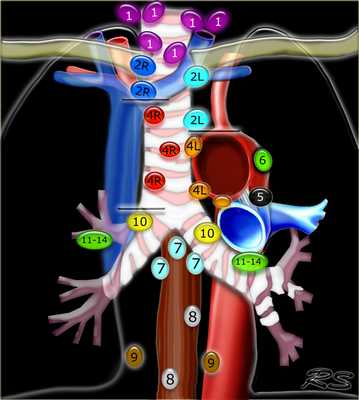

Лимфатические узлы 3 группы не примыкают к трахее в отличии от лимфатических узлов 2 группы. Они подразделюятся на: 3А кпереди от сосудов 3Р позади пищевода/превертебрально Они не доступны при медиастиноскопии. 3Р группа может быть доступна при чреспищеводной эхокардиографии.

На изображении слева 3А узел в преваскулярном пространстве. Обратите внимание так же на ниже расположенные паратрахеальные узлы справа относящиеся к 4R группе.

4R. Правые нижние паратрахеальные лимфатические узлы

- Верхняя граница: пересечение нижнего края левой плечеголовной вены с трахеей.

- Нижняя граница: нижний края непарной вены. 4R узлы распространяются до левого края трахеи.

На изображении слева мы видим 4R паратрахеальные узлы. Кроме того здесь представлен узел кнаружи от дуги аорты, то есть 6 группы.

4L. Левые нижние паратрахеальные лимфатические узлы

4L узлы расположенные слева от левой стенки трахеи, между горизонтальными линиями проведенными касательно верхней стенке дуги аорты и линией проходящей через левый главный бронх на уровне верхнего края верхнедолевого бронха. Они включают паратрахеальные узлы расположенные кнутри от артериальной связки.

Узлы 5 группы (аортопульмонального окна) расположены кнаружи от артериальной связки.

На левом изображении над уровнем легочного ствола представлены нижние паратрахеальные узлы слева и справа, так же здесь представлены узлы 3 и 5 групп.

Изображение слева выше уровня карины. Слева от трахеи 4L узлы. Обратите внимание что они расположены между легочным стволом и аортой, но не в аортопульмональном окне, потому что они лежат медиальнее артериальной связки. Лимфатические узлы латеральнее легочного ствола относятся к 5 группе.

- 5. Субаортальные лимфатические узлы

- Субаортальное или аортопульмональное окно расположено кнаружи от артериальной связки и проксимальнее первой ветви левой легочной артерии и лежит в пределах медиастинальной плевры.

- Парааортальные лимфатические узлы лежат кпереди и кнаружи от восходящего отдела аорты и между верхним и нижним краями дуги аорты.